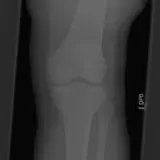

Over 2,100 interactive radiology cases, curated by radiologists for your level of training. Scroll, window, and view cases full screen — just like on PACS. Click linked findings in each writeup to jump straight to them on the image. Cases include sample reports, a focused discussion section, original illustrations, and videos.

完全交互式病例,配备您在 PACS 上期待的各项工具——滚动、调窗、缩放、平移、测量、ROI 和全屏模式。

丰富的标注直接在病例图像上突出关键发现。点击病例讲解中的关联发现,即可跳转至其在扫描上的精确位置。

交互式病例

像在工作站 PAC 上一样滚动、平移、调窗和缩放

通过标注的影像发现与示意图高效学习